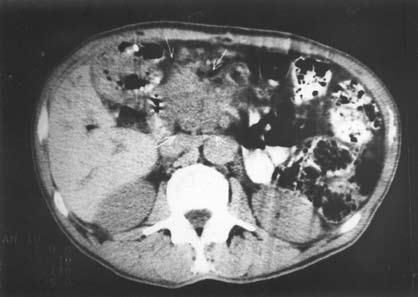

К сожалению, и специальные методы не во всех случаях позволяют решить рассматриваемую дифференциально-диагностическую задачу. Так, исследование крови больного на карбогидратный антиген (СА19-9) и раковый эмбриональный антиген (РЭА) дает отчетливо положительный ответ лишь при достаточно больших размерах опухоли, часто в неоперабельных случаях. Исследование ПЖ с помощью ультразвука или на компьютерном томографе дает увеличение размеров железы, в особенности ее головки, и при ХП, и при раке, а также выявляет очаговые образования тех или иных размеров, причем для рака более характерно одиночное гипоэхогенное образование, а при ХП поджелудочная железа чаще изменена диффузно, она гиперэхогенна (более плотная), содержит множественные кальцификаты (см. рис. 137–139), хотя точно дифференцировать характер очагов удается далеко не во всех случаях. Трудности дифференциальной диагностики ХП и рака ПЖ по данным УЗИ и КТ иллюстрируют рисунки 142–145.

Рис. 145. Компьютерная томография. Хронический псевдотуморозный панкреатит.

На снимке видна гиподенсная бугристая, с нечеткими контурами "опухоль" головки ПЖ 5x6 см (1)